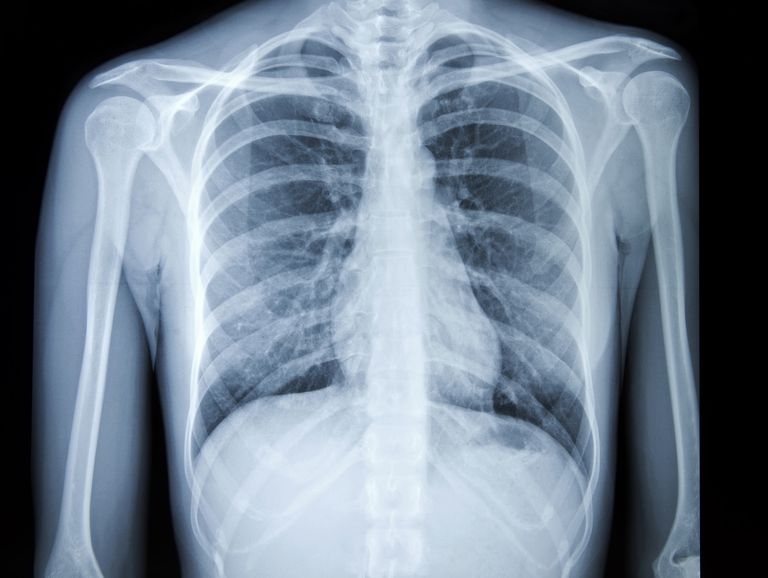

Как лечат рак легких в Израиле

Чаще всего узелки в легких, выявленные во время компьютерной томографии, являются доброкачественными новообразованиями. Свыше 90% таких узелков не представляют никакой опасности. С другой стороны, 90% раковых опухолей на ранней стадии можно вылечить с помощью одной только хирургической резекции. Именно так во многих случаях происходит лечение рака легких в Израиле. При необходимости пациенту назначаются другие методы лечения, которые подбираются индивидуально консилиумом специалистов.

Если израильский врач по результатам низкодозной компьютерной томографии подозревает, что у пациента рак легких на ранней стадии, больному проводится дополнительная диагностика и при необходимости — лечение.